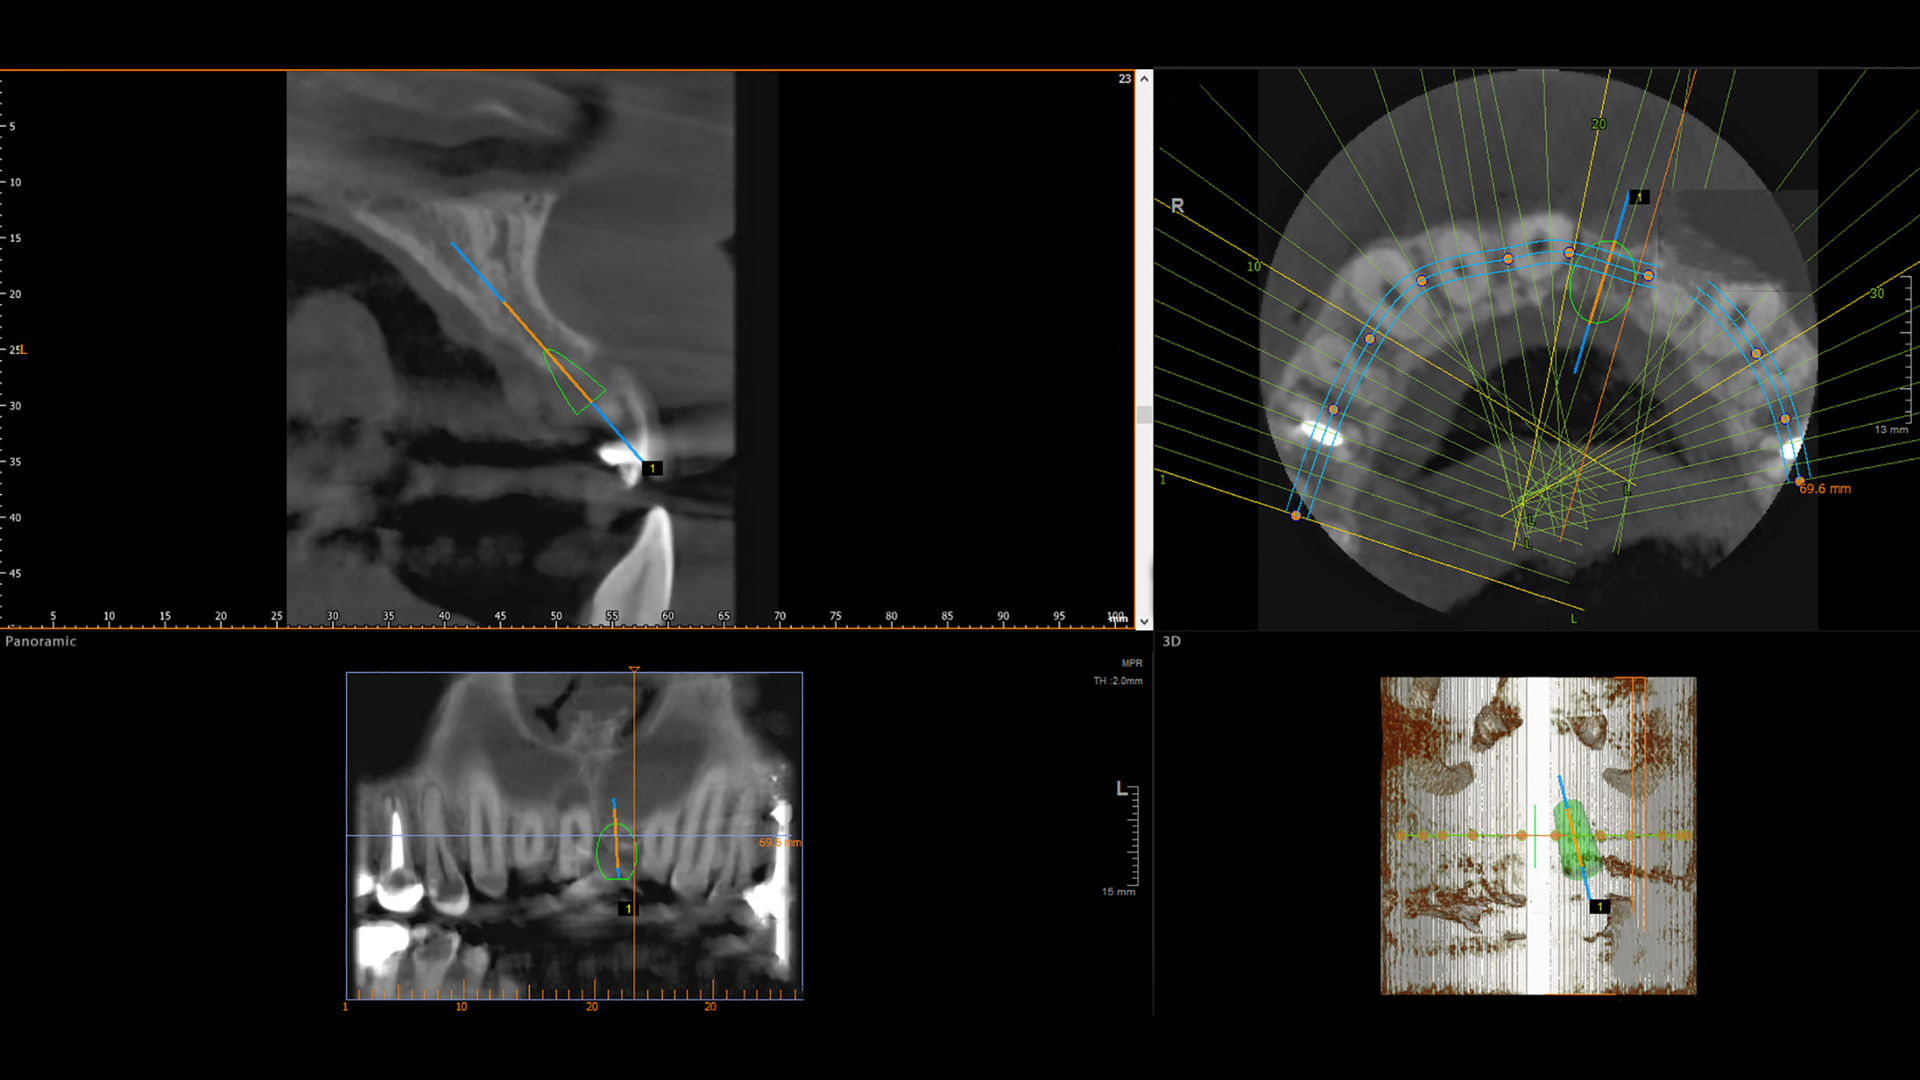

CBCTs have been used to help diagnose and treat patients within the last 20 years, and as such are considered a newer technology. A CBCT is similar to a medical computer tomography (CT) scan, but with a lower level of radiation and specifically adapted for oral health care.1,4 A CBCT is a unique digital image that uses computer software to help combine about 600 images into one giant voxel—voxel is a pixel in a 3D view—resulting in a 3D image that captures both hard and soft tissues.5

CBCTs are very useful among certain dental specialists.1 (Currently, none of these specialists are RDHs.) Due to CBCTs’ defined ability to image bone shapes and contours of edentulous ridges in 3D, many oral surgeons turn to them to help with more accurate placement of a dental implant.1

Certain anatomy is difficult to view on a 2D radiograph, such as the maxillary sinus and inferior alveolar nerve. These structures can be seen in vivid detail on a CBCT, so many oral surgeons find them more reliable for their patient treatment plans.1 CBCTs are also not recommended for evaluating the location of third molars, except when extractions are needed, as panoramic radiographs adequately provide that information.1